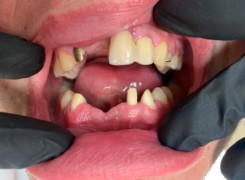

Pan Kamil zgłosił się do gabinetu po wypadku rowerowym w wyniku którego wybił ząb – lewą górną jedynkę. W takiej sytuacji została podjęta decyzja o implantacji natychmiastowej oraz zapatrzeniu pacjenta na czas integracji wszczepu w uzupełnienie tymczasowe.

Poniżej przebieg odbudowy protetycznej.